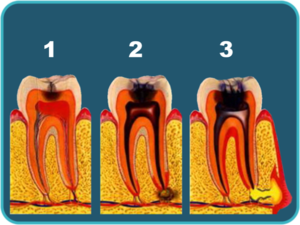

Кариес (некроз под действием м/о твердых тканей зуба) начинается со стадии «пятна» →поверхностный кариес → средний кариес → глубокий кариес → пульпит (воспаление («нерва») пульпы зуба) → периодонтит (воспаление периодонта)